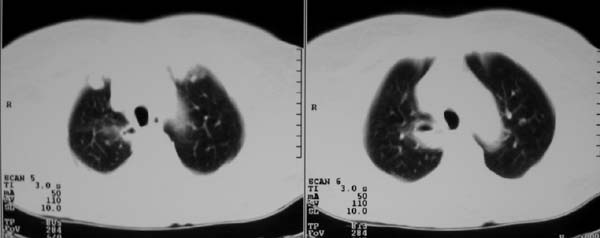

以下是引用zjzjr在2007-8-30 22:22:00的发言:[br]右上肺肺囊肿合并感染.右下肺肺大泡.左肺舌段感染.